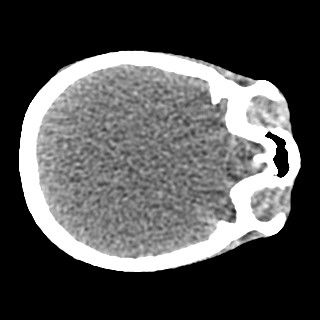

Cone-beam CT (CBCT) employs a flat-panel detector to achieve three-dimensional imaging with high spatial resolution. However, CBCT is susceptible to scatter during data acquisition, which introduces CT value bias and reduced tissue contrast in the reconstructed images, ultimately degrading diagnostic accuracy. To address this issue, we propose a deep learning-based scatter artifact correction method inspired by physical prior knowledge. Leveraging the fact that the observed point scatter probability density distribution exhibits rotational symmetry in the projection domain. The method uses Gaussian Radial Basis Functions (RBF) to model the point scatter function and embeds it into the Kolmogorov-Arnold Networks (KAN) layer, which provides efficient nonlinear mapping capabilities for learning high-dimensional scatter features. By incorporating the physical characteristics of the scattered photon distribution together with the complex function mapping capacity of KAN, the model improves its ability to accurately represent scatter. The effectiveness of the method is validated through both synthetic and real-scan experiments. Experimental results show that the model can effectively correct the scatter artifacts in the reconstructed images and is superior to the current methods in terms of quantitative metrics.